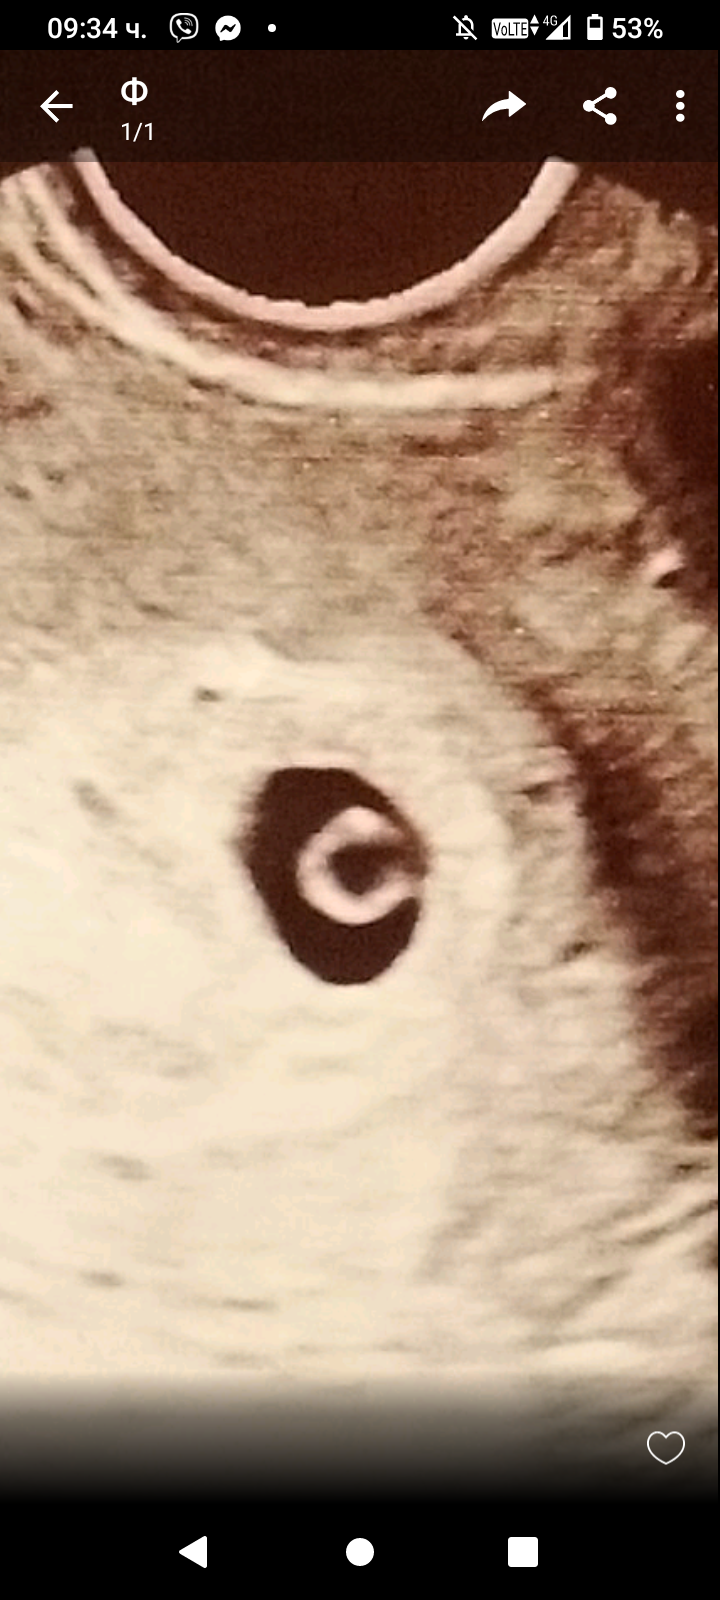

Какво представлява изображението от ехографията на 5-седмична и 2-дневна бременност?